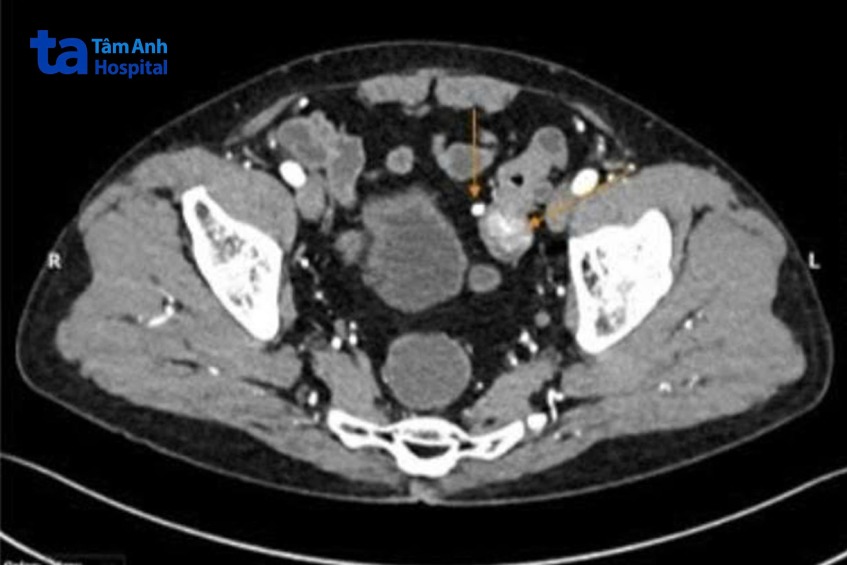

Trước đó, ông Châu (ngụ tại Đồng Tháp) không có triệu chứng bệnh rõ ràng, chỉ thỉnh thoảng đầy hơi, đi ngoài phân hơi nhỏ, dẹt. Ông đến Phòng khám Đa khoa Tâm Anh Quận 7 khám tổng quát. Kết quả chụp CT hơn 100.000 lát cắt ghi nhận có cấu trúc bất thường làm dày thành đại tràng sigma (vị trí thấp nhất trong đại tràng, nối liền với trực tràng), kích thước 2,5 cm.

Nghi ngờ tổn thương nguy hiểm, tiến sĩ bác sĩ Đỗ Minh Hùng, Giám đốc Trung tâm Nội soi và Phẫu thuật Nội soi Tiêu hóa, Bệnh viện Đa khoa Tâm Anh TP HCM, chỉ định ông Châu nội soi đại tràng bằng hệ thống nội soi phóng đại 150 lần để đánh giá xác định chuyên sâu. Kết quả ghi nhận ông Châu có nhiều polyp dọc khung đại tràng, trong đó, polyp lớn 2,5 cm nằm chặn ở đại tràng sigma, bề mặt polyp biến đổi cấu trúc tuyến và vi mạch máu, nghi ngờ ung thư. Bác sĩ tiến hành lấy mẫu sinh thiết polyp ngay trong lúc nội soi, đồng thời cắt hết các polyp nhỏ để phòng ngừa polyp tiến triển hóa ác về sau.

Kết quả giải phẫu bệnh là ung thư biểu mô tuyến xâm nhập, tế bào ung thư đã tiến triển, nguy cơ cao di căn đến các hạch bạch huyết gần đó hoặc các cơ quan xa hơn trong cơ thể. “Người bệnh cần phẫu thuật lấy u, nạo vét hạch bạch huyết càng sớm càng tốt để ngăn ngừa tế bào ung thư lan rộng”, bác sĩ Minh Hùng nói, thêm rằng gần đây nhiều trường hợp phát hiện ung thư đại tràng nhờ chỉ dấu từ chụp CT như ông Châu. Hiện các thế hệ máy CT mới với số lát cắt lớn, tích hợp AI có khả năng nhận diện nhanh các tổn thương trong cơ thể, qua đó giúp bác sĩ kịp thời chẩn đoán các bệnh nguy hiểm.